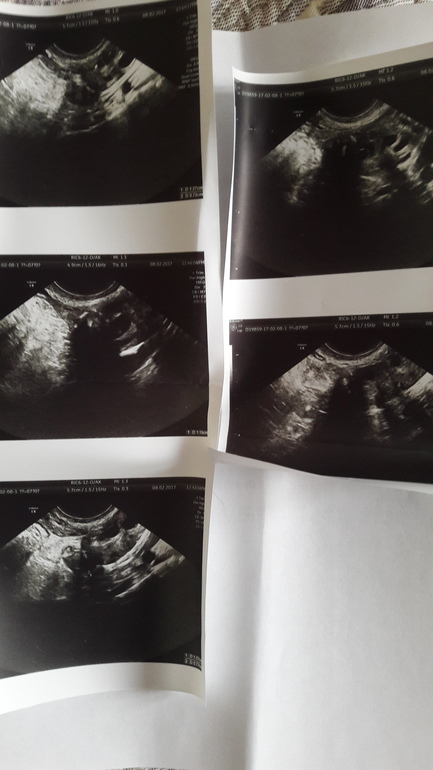

Узи проводили влагалищным датчиком.

вот фото.гормоны сдала по собственной инициативе,т.к врач в жк говорит что мне ничего не надо сдавать. Узи делала в платной клинике. Теперь думаю туда записаться на прием к репродуктологу

Яичники однозначно поликистозные, видно даже по объему. Вам надо обратиться к гинекологу, можно к репродуктологу, но по поводу трубы необходимо уточнить. Может врач сам пересмотрит, на фото не могу ничего сказать по этому поводу